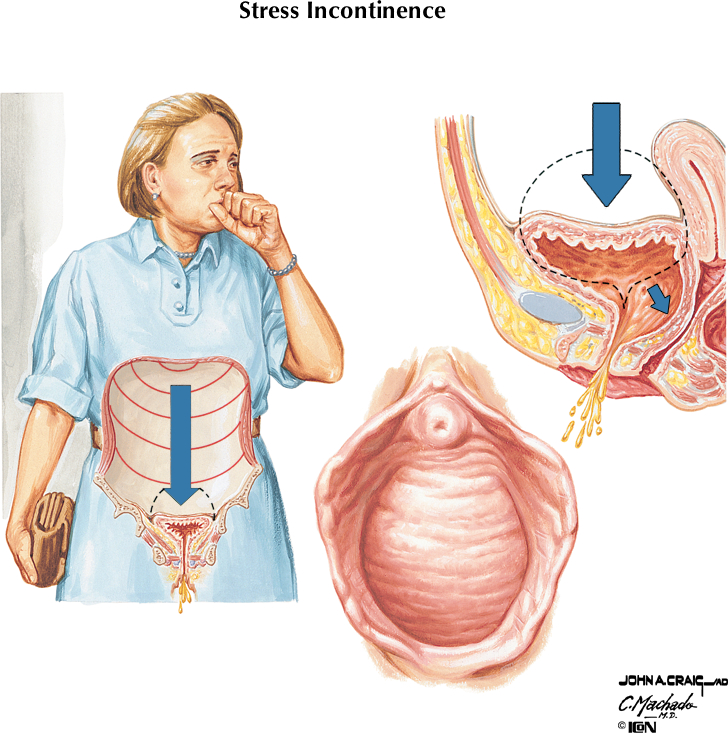

- Stresová inkontinencia moču – jedná sa o mimovoľný únik moču u žien počas fyzických aktivít ako cvičenie, tancovanie, zdvíhanie bremien alebo kýchanie a kašľanie. Vzniká pri poruchách panvového dna (napr.: po pôrode, operácií, poškodení nervov).

Aplikácia suburetrálnej pásky pomocou transobturátorového prístupu predstavuje účinné a rýchle riešenie stredne ťažkej až ťažkej stresovej inkontinencie. Hlavnou výhodou je okamžitý efekt – väčšina žien má schopnosť udržať moč takmer okamžite po operácii, čo vedie k výraznému zlepšeniu komfortu aj sebavedomia.

Ako prebieha operačná liečba úniku moču?

Operačná liečba stresovej inkontinencie moču vyžaduje krátkodobú hospitalizáciu do 24 hodín. Vykováva sa v celkovej anestézii. Pred operáciou absolvuje pacientka diagnostiku inkontinencie moču, kde presne definujeme typ a stupeň inkontinencie moču a na základe výsledkov doporučíme optimálny postup.

V prípade ťažších foriem stresovej inkontinencie moču (únik moču pri kašli, smiechu, behu ale aj pri inej bežnej fyzickej aktivite) s výraznejšou spotrebou vložiek a dobrom celkovom zdravotnom stave bez výraznejších komplikujúcich faktorov doporučíme operačné riešenie. Po absolvovaní interného a anesteziologického predoperačného vyšetrenia vykonáme operačné riešenie.

Samotná operácia trvá obvykle do 20-30 minút. Naše pracovisko vykonáva liečbu za použitia certifikovanej suburetrálnej pásky ARIS renomovaného výrobcu COLOPLAST. Po operácii vznikajú 2 malé 1 cm jazvy v kožnej ryhe medzi stehnom a ohambím a malá 2 cm jazva na prednej pošvovej stene. Jazvy sa obvykle dobre hoja a po niekoľkých mesiacoch od operácie ich obvykle nie je poznať.

Pacientka odchádza z nemocnice domov do 24 hodín. Po týždňovej práceneschopnosti je možné obvykle nastúpiť do práce. Radíme 3 mesačné fyzické šetrenie, bez zdvíhania ťažkých bremien a 4 týždňovú sexuálnu abstinenciu. Výsledkom operácie je vymiznutie úniku moču ihneď po operácii. V pooperačnom období môže pacientka pociťovať mierne napätie v oblasti operačných rán, ktoré obvykle do 2 mesiacov vymizne.